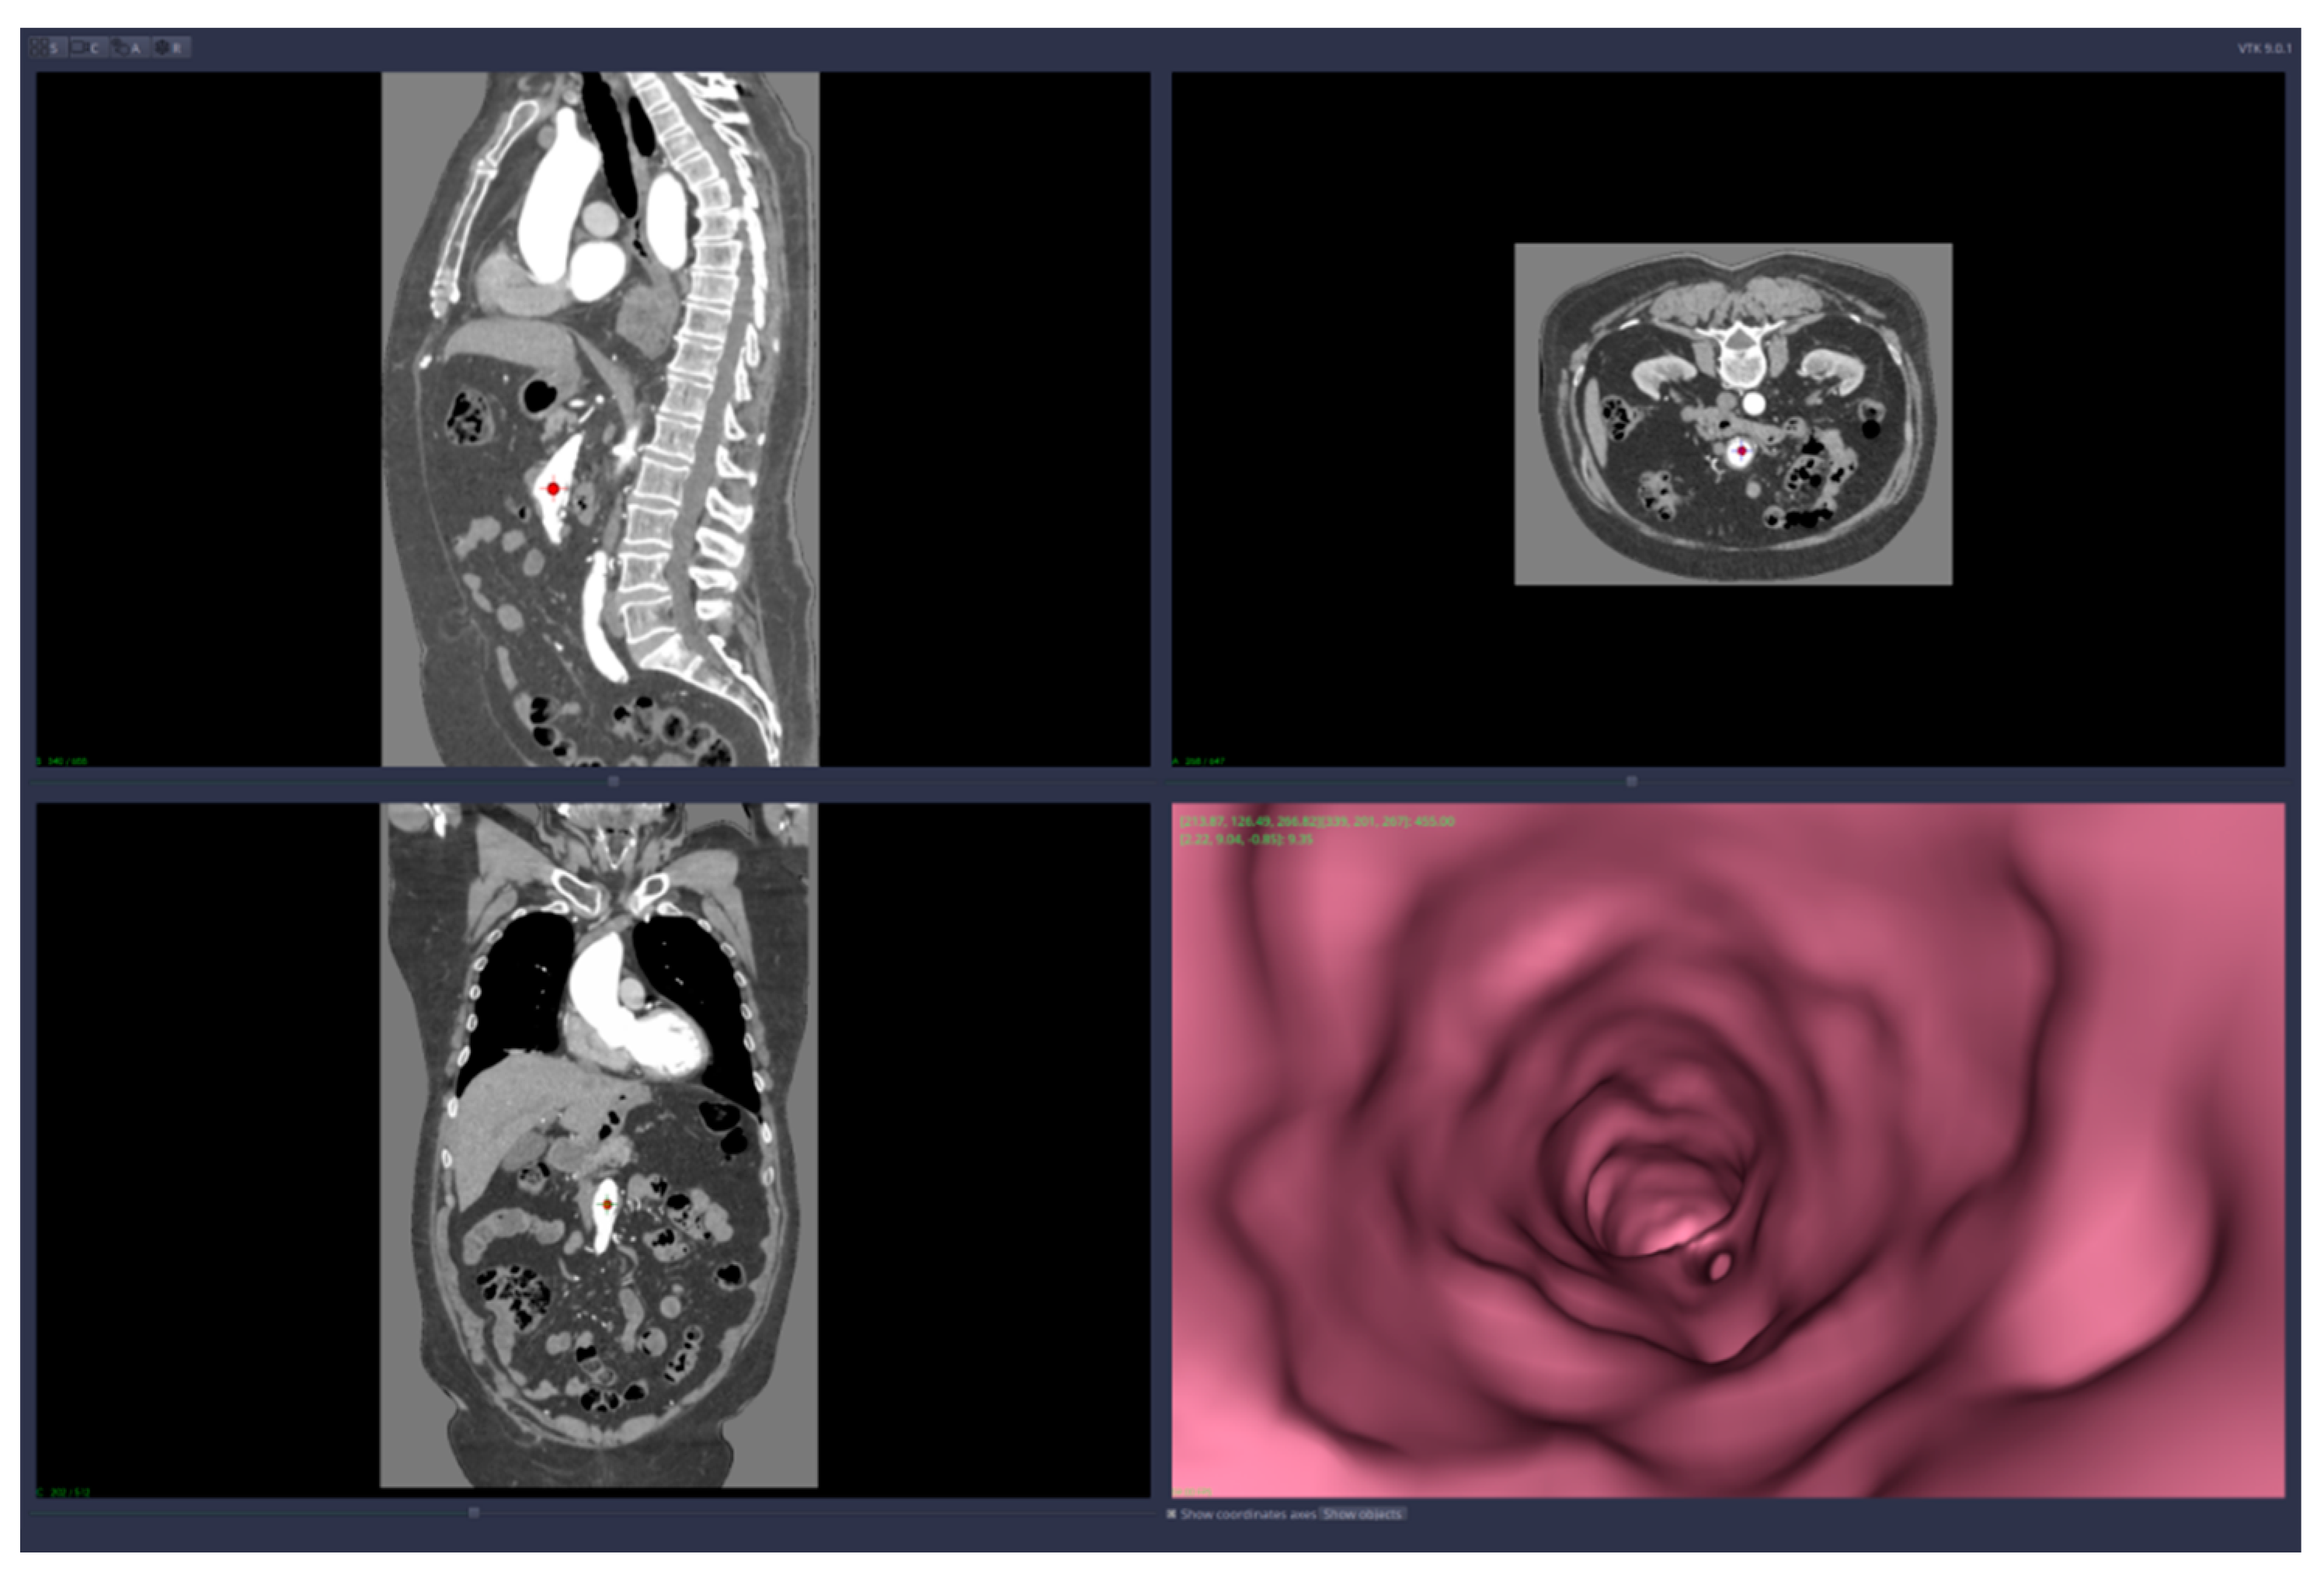

• Virtual angiography—virtual 3D navigation through the mesenteric artery and aneurysm zone (see Figure 3, Figure 4, Figure 5, Figure 6 and Figure 7)

Virtual angiography means that the user is able to navigate inside the artery using only the computer mouse device. The navigation starts from a point chosen by the user and the virtual camera is forced to remain inside the artery walls. The algorithm that implements this restriction on the virtual camera is based on collision detection and resolution directly on voxels (no segmentation is required). The path of the virtual angiography can be saved and used later, in other planning sessions.

Figure 3. Virtual angiography—“normal” zone of the mesenteric artery, before the aneurysm (direction is opposite to the blood flow).

Figure 4. Virtual angiography—inside the mesenteric artery aneurysm (direction is opposite to the blood flow).

Figure 5. Virtual angiography—“normal” zone of the mesenteric artery, after the aneurysm (direction is opposite to the blood flow).